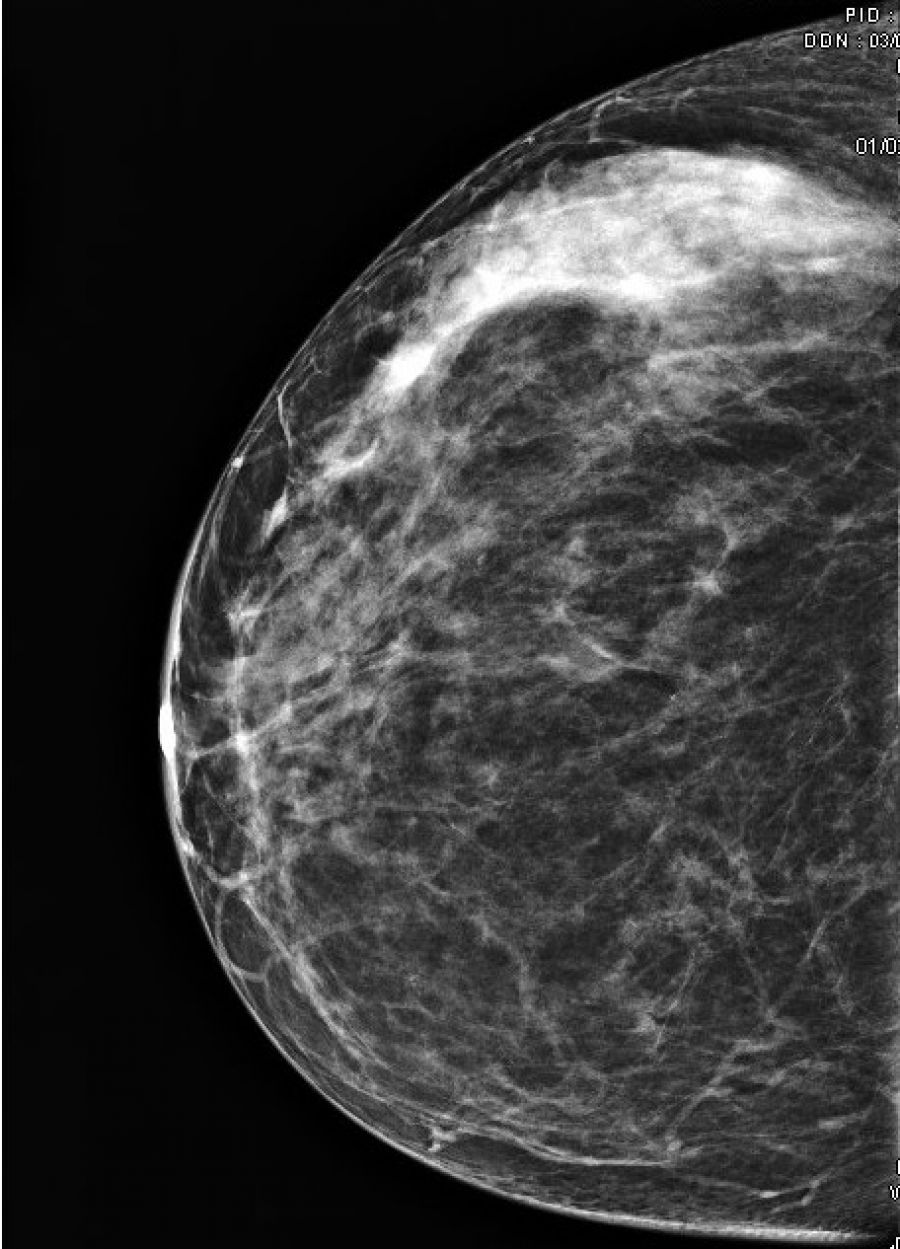

La mammographie est une exploration des seins utilisant les rayons X. Elle est réalisée sur un appareil spécifique situé dans un local exclusivement destiné à cet examen.

L’examen comporte 2 ou 3 clichés sur chaque sein. La compression du sein est nécessaire pour améliorer la qualité des clichés, donc l'efficacité du diagnostic radiologique. La compression est un peu désagréable. Elle est très rarement douloureuse. Si c'est le cas, la manipulatrice cessera immédiatement la compression.

• Ce premier bilan pourra être complété par d'autres clichés ou par une échographie pour être plus précis sur certains diagnostics.

La technique utilisée est celle de la radiographie, mais avec un faisceau de plus faible énergie (baisse du kilovoltage).